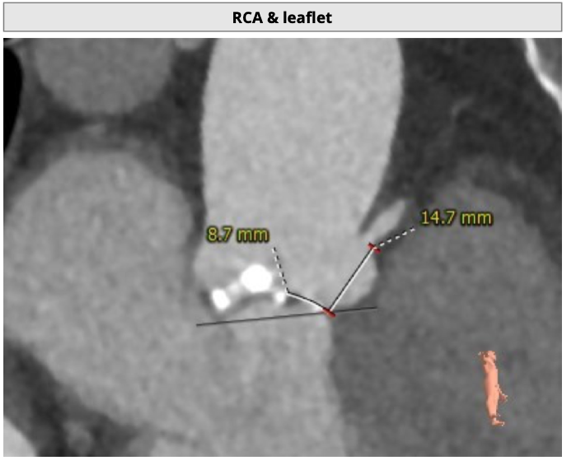

主动脉根部评估

CT 数据显示该患者为Type1型二叶式主动脉瓣

主动脉瓣瓣环周长72.5mm,周长径23.1mm

LVOT 周长 85.1mm,周长径27.1mm

SOV:31.1mm*33.6mm*31.6mm

STJ 周长 91.9mm

无冠瓣钙化严重,HU850:448mm³

瓣环水平夹角46度